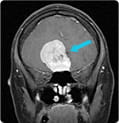

Olfactory Groove Meningioma

Traditional surgery for an olfactory groove meningioma would require a long scalp incision and lifting the front of the brain to get to the tumor. In the case of a 35-year-old woman experiencing headache and vision loss from pressure and swelling in her brain, the tumor, because of its height, required a long reach to the top of the tumor. Read how UPMC surgeons used EEA to remove the tumor without lifting the brain.